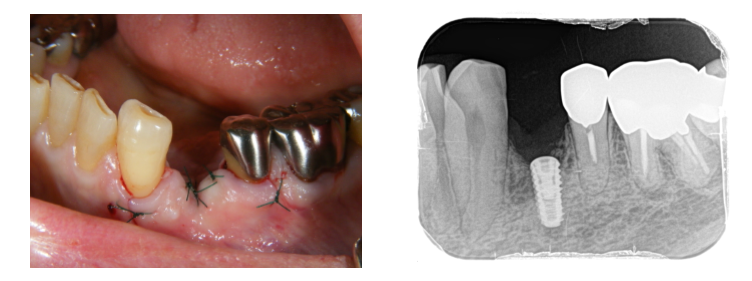

歯根破折して、歯の周りの骨が下がっています。

状態が悪く、保存できなかったため、抜歯することになりました。

2か月、歯肉の傷の治りを待ちました。

レントゲン、CT診査にて、骨の幅が少なかったため

埋め込みと同時に骨幅を増やすGBR(骨誘導再生法)を行うことにしました。

埋入直後の写真です。

少し歯肉を開いて、骨造成しています。麻酔は、普通の歯科治療の局部麻酔です。

1週間で抜糸し、その後2か月ほど待ちます。